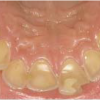

Mao ülehappesuse ja reflukshaiguse korral põhjustab suhu sattuv maohape lisaks limaskesta söövitamisele ka hammaste erosiooni (fotol näha maohappest põhjustatud ülemiste hammaste sisepinnna söövitus reflukshaigel).

Refluksi korral on neelu tagaseina limaskest punetav - see on tingitud happe ärritusest. Neid sümptome on kogenud hambaarstil kerge märgata ja suunata patsient vajadusel edasistele uuringutele oma pere- või eriarsti juurde.